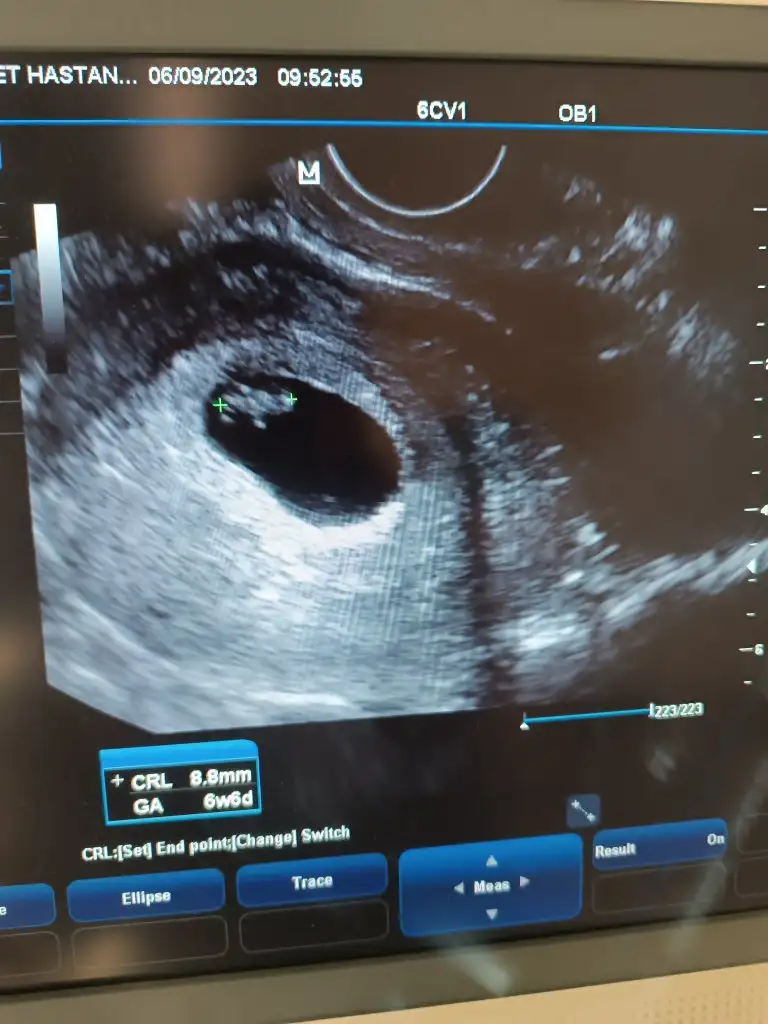

Bizi de yorumlarmısınız 6+6 günlük vajinal usg. Şuan 10 haftalık olduk. Hareketlerini hissediyorum. Kelebek gibi his veriyor sag sol fark etmiyor. Göbek altı veya yanın da kıpırdıypr bazen

• Screenshot_2023-09-06-12-36-22-050_pixelab.black.camera.webp

Screenshot_2023-09-06-12-36-22-050_pixelab.black.camera.webp

22,7 KB · Görüntüleme: 218